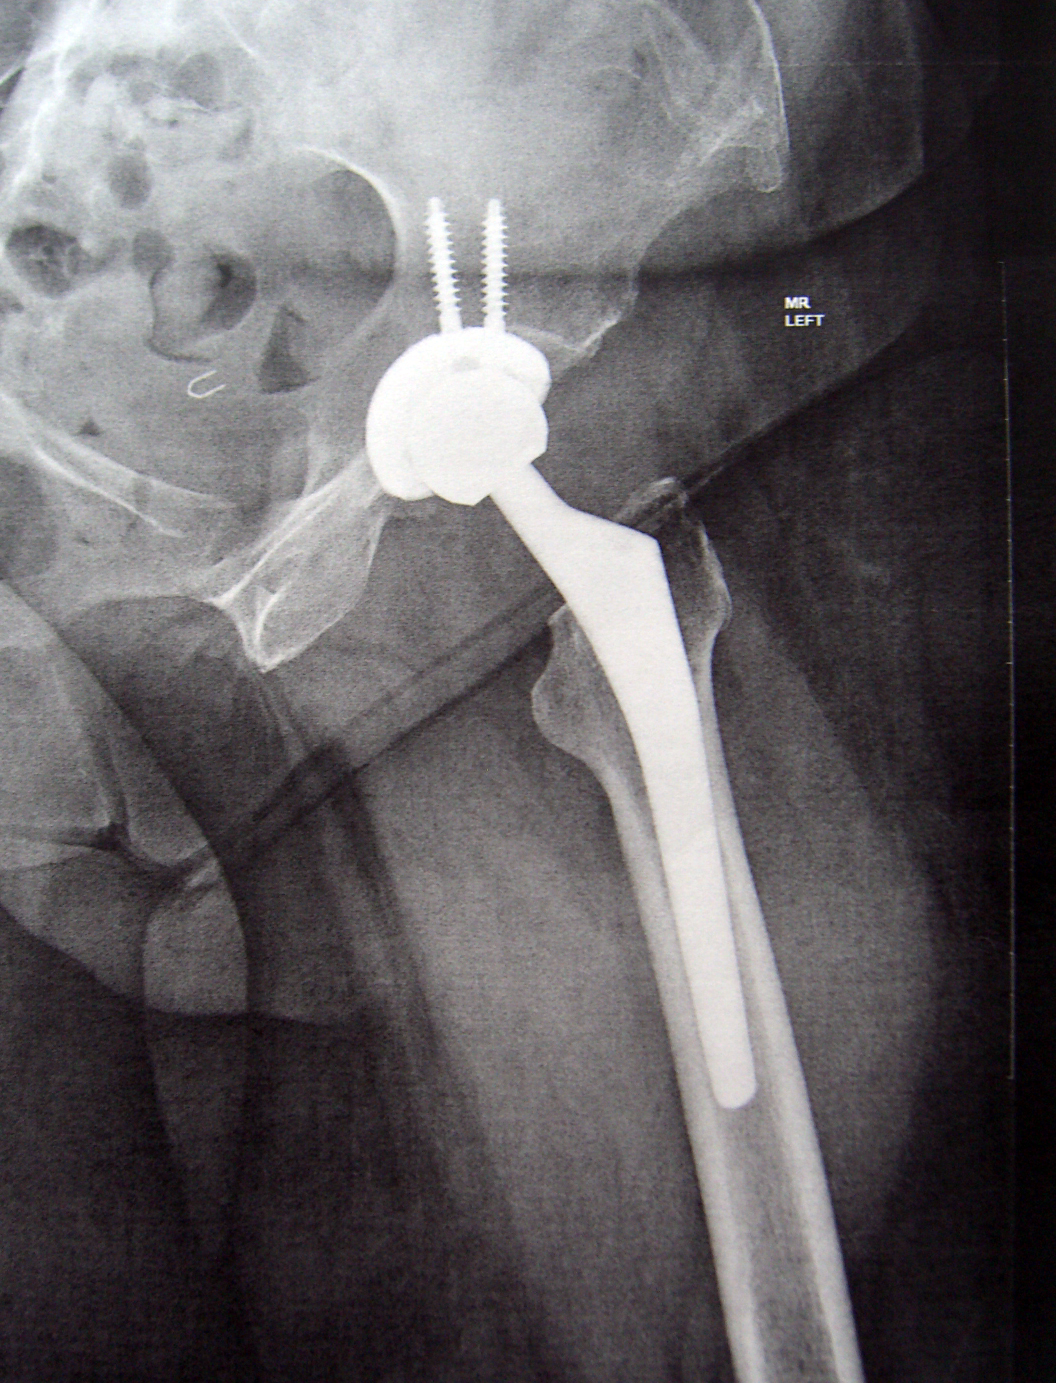

My New HIp. 14th April 2015  by Dr. Springer, OrthoCarolina

Another view of my New Hip - by Dr. Springer - OrthoCarolina

Another view of my New Hip – by Dr. Springer – OrthoCarolina